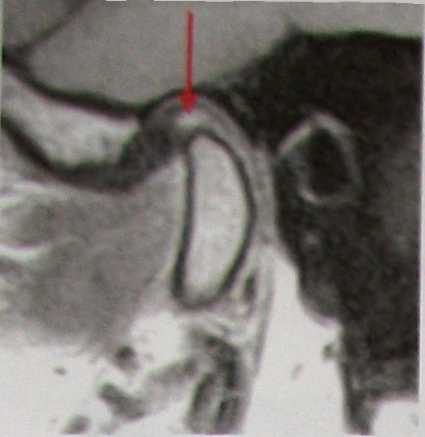

| Рис.8.73. Т1 взвешенная МРТ ВНЧС в кососагиттальной проекции. Дегенеративные изменения (стрелка) в промежуточной зоне недеформированного нормально расположенного диска. |

Наличие дегенеративных изменений в промежуточной зоне недеформированного диска — весьма распространенная патология у всех пациентов, проходящих ортопедическое или ортодонтическое лечение (рис.8.73) При отсутствии клинической симптоматики описанные дегенеративные изменения диска рассматриваются как проявления доклинической функциональной перегрузки сустава в связи с тем, что промежуточная зона диска несет наибольшую функциональную нагрузку; в норме постоянно разобщая бугорок височной кости и мыщелок ветви нижней челюсти.